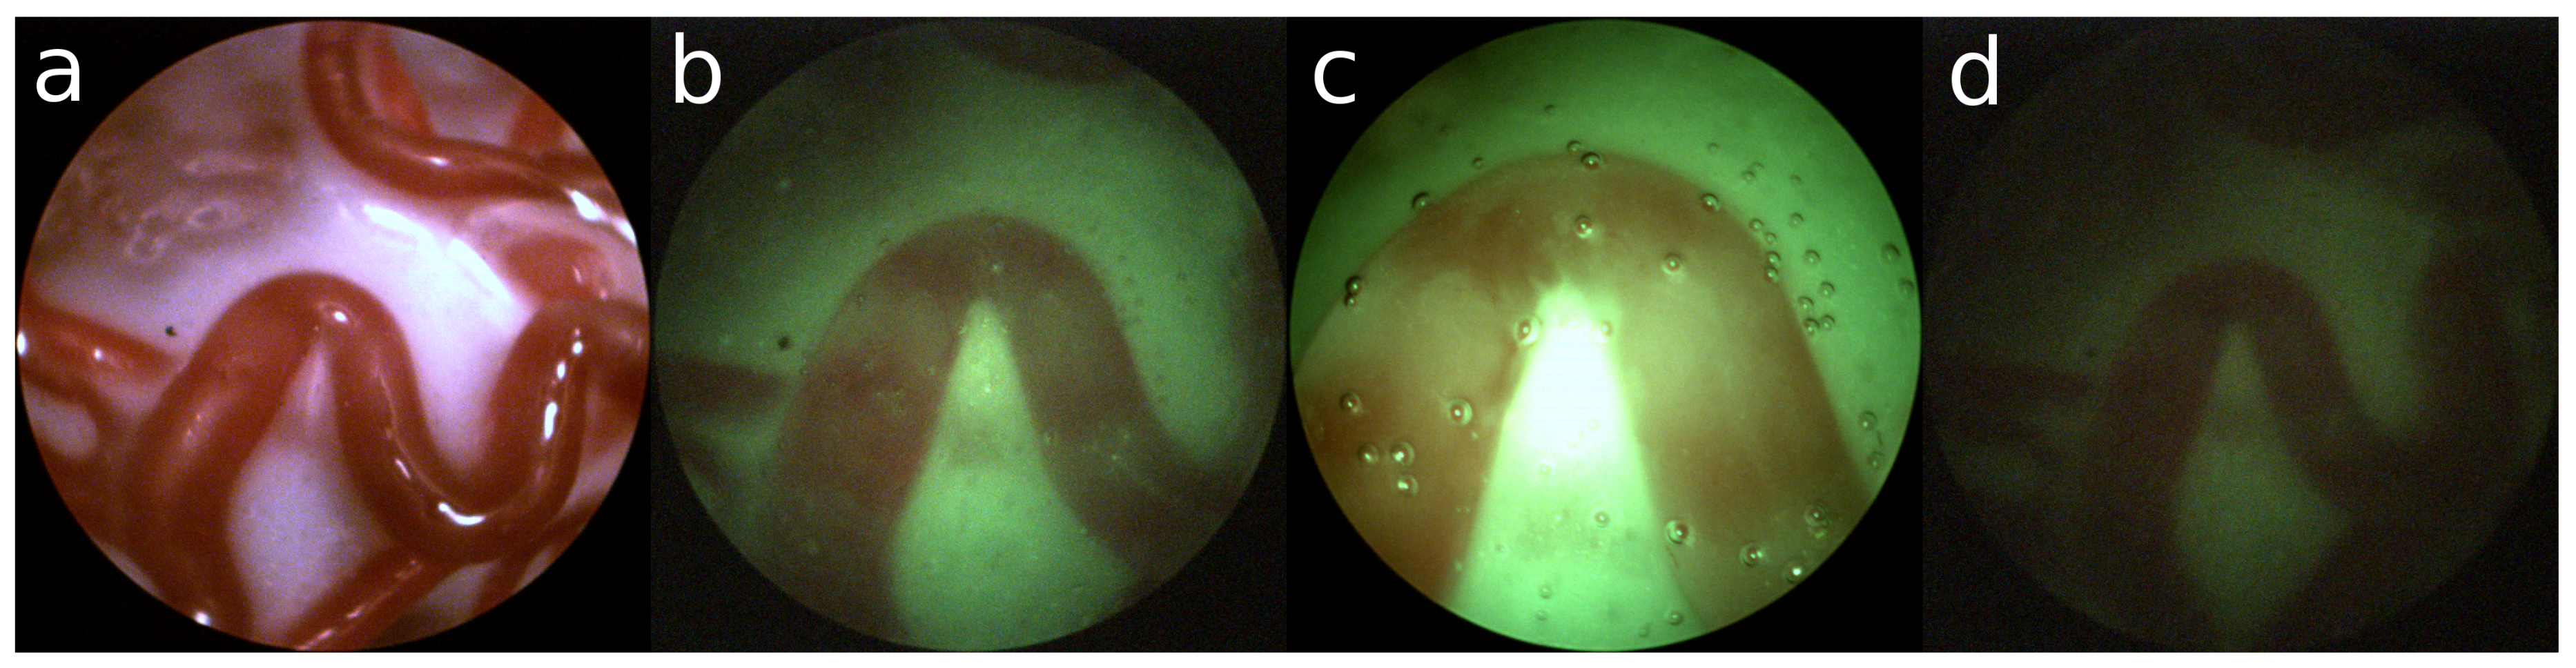

• Also, the fetus and particles that float in the amniotic can limit the field of view of the view of the placenta. In Figure 1c and Figure 2c air bubbles can be observed. However, these are the result of using water in mimicking the in-vivo setting and are not part of the surgical setting.

• The source of light is the fetoscope itself. This results in an uneven distribution of light, which reduces the amount of illumination towards the edge of the view. Furthermore, saturation of the imaging sensor in the center of the image inhibits proper observation of the structure of the placenta.

Examples are shown in Figure 1. Especially for the green turbid liquid it is difficult for the camera to acquire a proper image, resulting in a large amount of sensor noise.

Figure 2a shows an example of an ex-vivo setting with a satisfactory amount of structure. In contrast, Figure 2b shows a nominal example of an in-vivo setting with green turbid liquid. From this point of view, the fetoscope can be moved laterally resulting in a closer view (Figure 2c) or more distant view (Figure 2d). One can observe that suboptimal viewing conditions are unavoidable in an in-vivo setting.

Figure 1. (a) Ex-vivo view; (b) uneven distribution of light; (c) too much light saturating the sensor; (d) not enough light creating sensor noise.

Figure 2. Ex-vivo: (a) sufficient structure; In-vivo: (b) nominal; (c) close and bright; (d) far and dark.